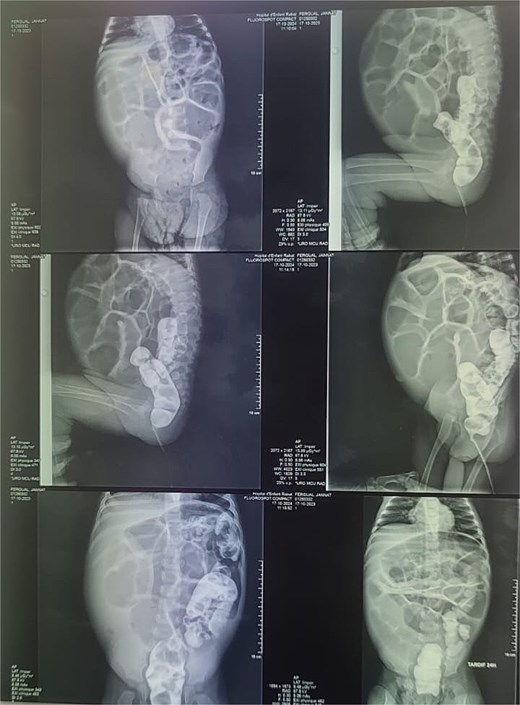

Reviewing the medical record of the patient, she underwent variable blood tests that were negative mostly except for ionogram disturbances due to malnutrition and dehydration. An abdominal X-ray was performed at each episode of hospitalization, that revealed intestinal-type hydroaeric levels and gastric stasis (Fig. 1) then a digestive fibroscopy with multiple biopsis as well as eosogastroduodenal transit were run out suggesting gastritis. A barium index (Fig. 2) was also performed on his last hospitalization suggesting a small bowel obstruction which also appeared on the Enteroscan (Fig. 3).

Enteroscan image showing an intestinal distension downstream of an obstacle.